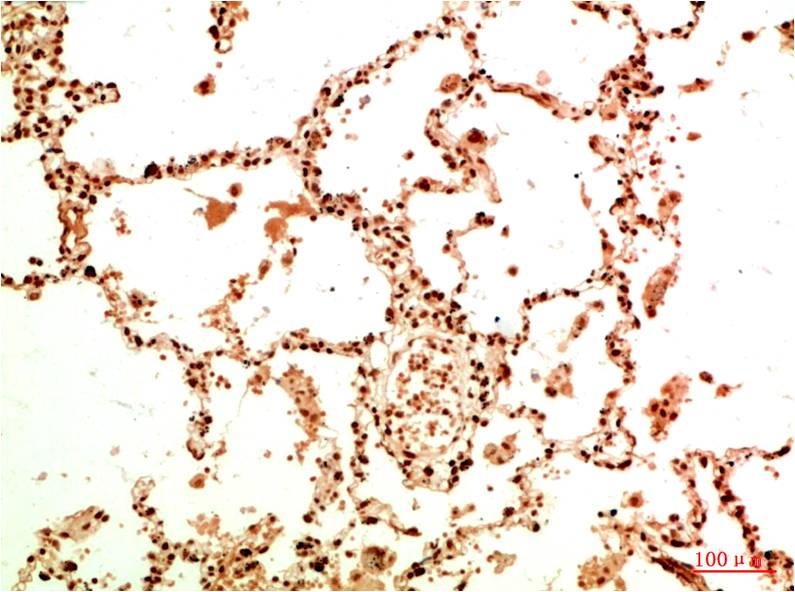

分类: 科研抗体货号: P20021别名: Antigen NY-CO-13; Cellular tumor antigen p53; Phosphoprotein p53; TP53; Tumor suppressor p53应用: WB,IP,IF反应种属: Human,Mouse,Rat